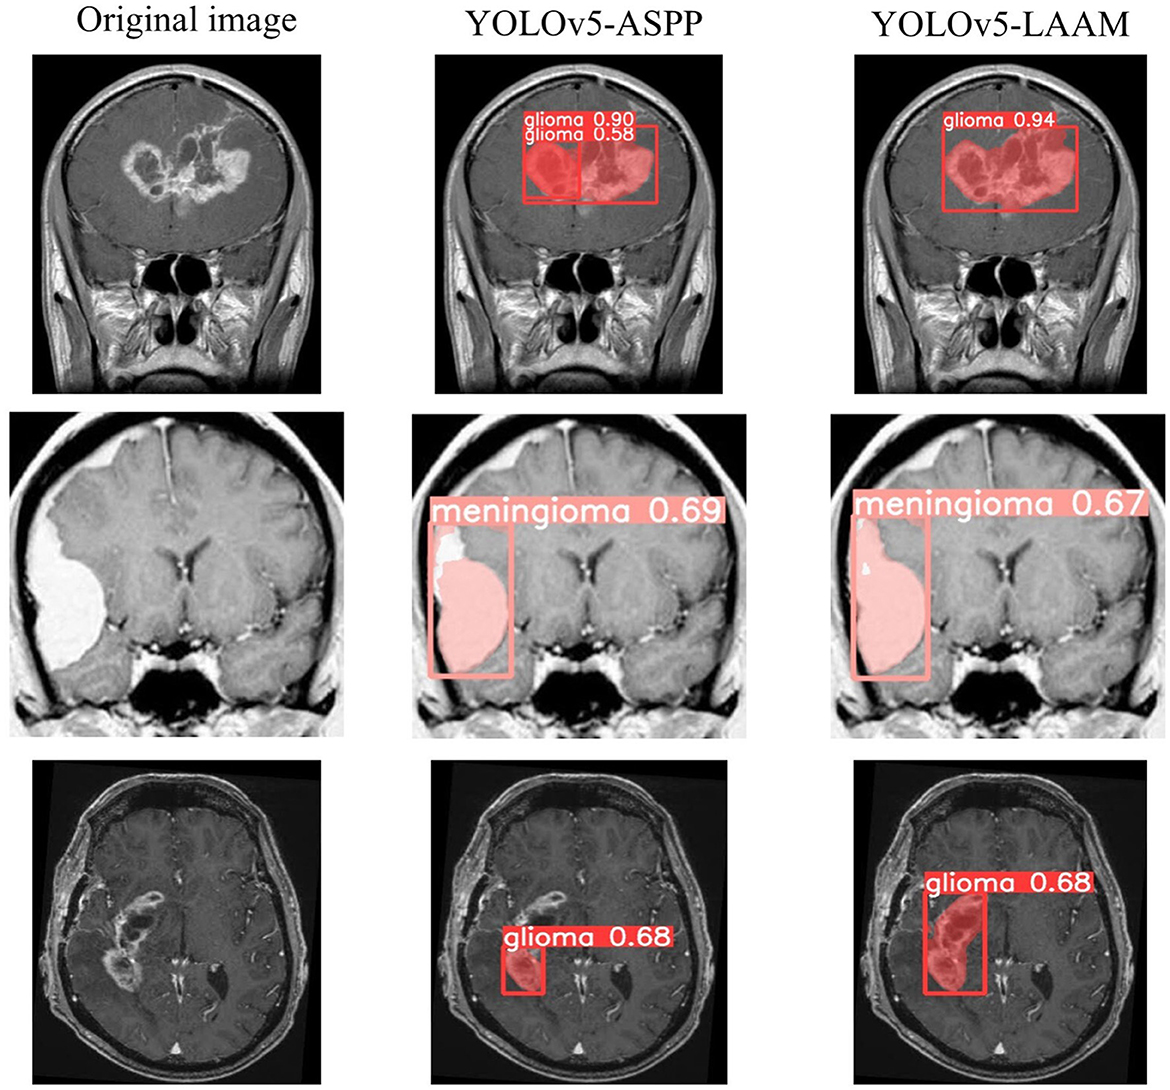

As shown in Tables 7, 8, on the internal test set, YOLOv5s-LAAM outperformed YOLOv5s-ASPP in both overall performance (mAP@50: 0.833) and recall rate (0.824), compared to the latter's scores (0.826 and 0.784, respectively). This indicates its superior lesion coverage capability and improved control over missed detections. Although its precision (0.748) on the external test set was lower than that of the ASPP variant (0.82), LAAM still maintained a higher recall rate (0.741). Furthermore, as illustrated in Figures 9, 10, it provided more complete and accurate localization and delineation of tumor regions.

Figure 9

Test results of YOLOv5-ASPP and YOLOv5-LAAM on the internal test set.

Figure 10

Test results of YOLOv5-ASPP and YOLOv5-LAAM on the external test set.